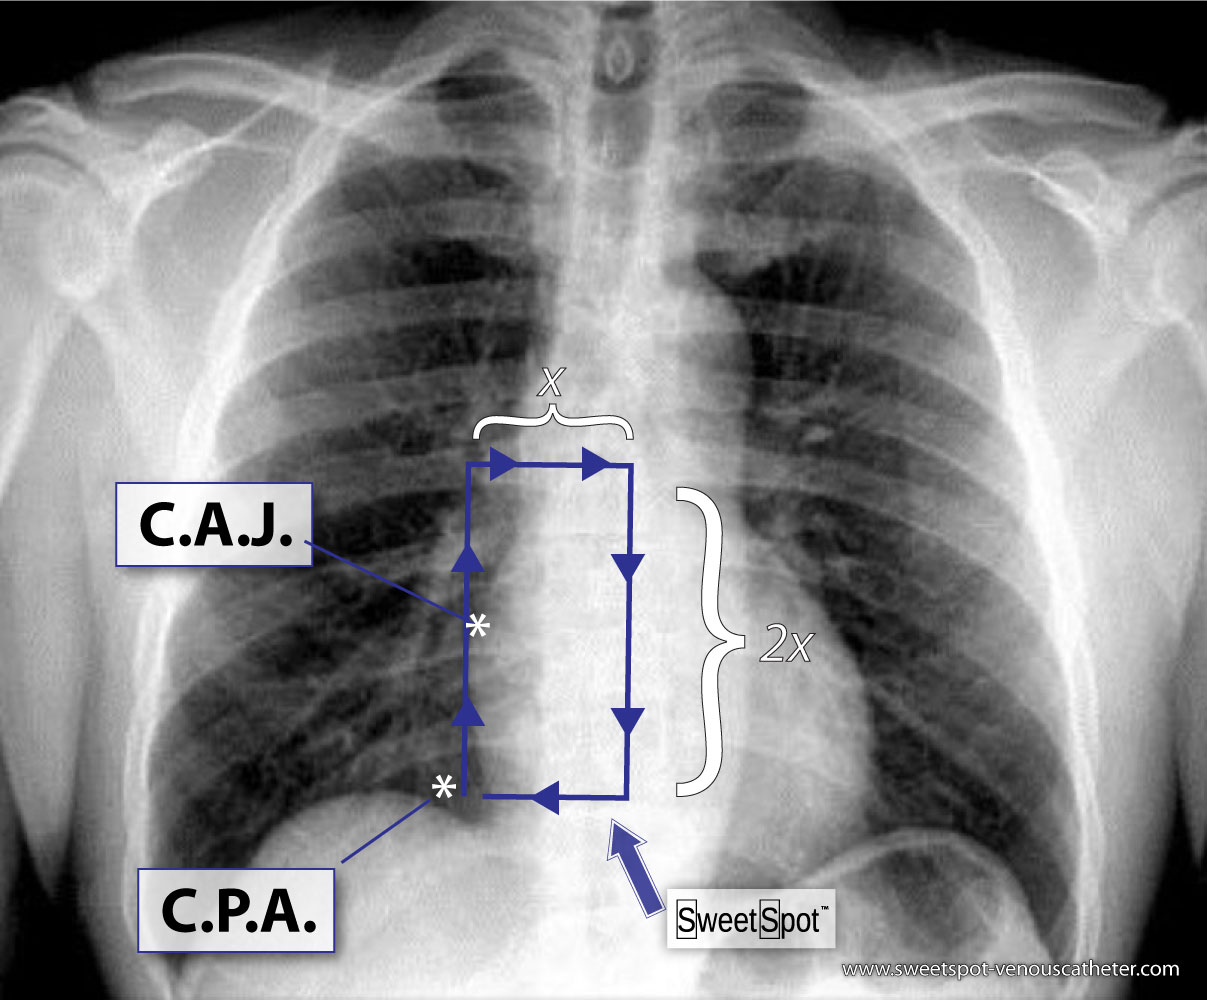

How to Draw the Sweet Spot™

1. On a frontal CXR, identify the CAJ and the right CPA.

2. Start at a point as close as possible to the CPA that permits a vertical line to be drawn along the right edge of the cardiac silhouette.

3. Go twice the distance of the CPA to the CAJ.

4. Next, continue a horizontal line to your right equaling one-half the length of the previous vertical line.

5. Lastly, turn inferiorly and complete the rectangle.